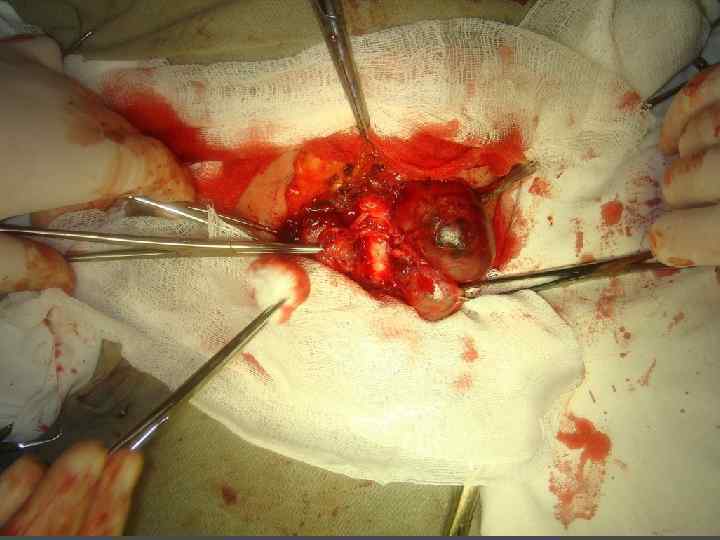

ХИРУРГИЧЕСКОЕ ЛЕЧЕНИЕ ЗОБА

ХИРУРГИЧЕСКОЕ ЛЕЧЕНИЕ ЗОБА

ОСЛОЖНЕНИЯ ХИРУРГИЧЕСКОГО ЛЕЧЕНИЯ ►Поражение возвратного нерва, приводящее к параличу голосовой связки на стороне поражения, как следствие – изменение тембра голоса, сужение голосовой щели, затруднение дыхания. ► Кровотечение. ►Тиреотоксический криз. ► Гипопаратиреоз. ► Рецидив тиреотоксикоза. ► Формирование порочного рубца.